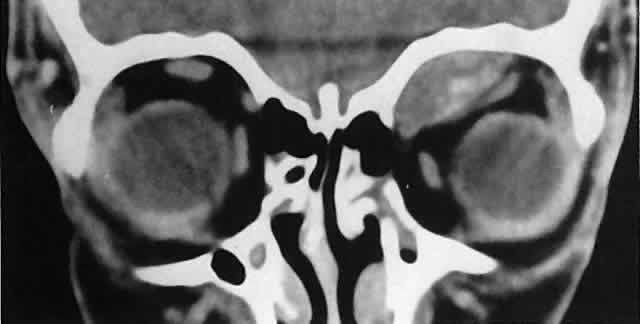

Orbital myositis may represent a greater proportion of cases of IIPT in childhood than in adulthood, and involvement of multiple extraocular muscles may occur more frequently in children than inadults. In orbital myositis, early diplopia and increased discomfort with attempted eye movement are typical symptoms. CT may show enlargement of one or more extraocular muscles in one or both orbits (Figs. 21 and 22). When a single muscle is involved, the specter of a primary or metastatic neoplasm within the muscle may be raised. However, external inflammatory signs, considerable pain and limited motility, and an explosive onset of symptoms within 24 hours all suggest orbital myositis. The uniform enlargement of the muscle, including its tendinous insertion (see Fig. 22), also helps distinguish the process from a neoplasm, which might be expected to produce a more focal, globular expansion. Echography may support the diagnosis of inflammation by showing edema in the episcleral space as a relative sonolucency between the scleral and orbital fat echoes (Fig. 23). Its CT counterpart is an increase in the radiodensity and thickness of the ocular tunica.

Fig. 22. The uniform enlargement of the left medial rectus muscle, including its tendinous insertion, is characteristic of orbital myositis.

Fig. 23. Acoustic discontinuity between the globe and the orbital fat indicates inflammatory edema in Tenon's space.